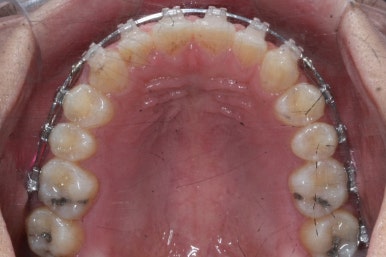

점점 앞니 사이의 틈이 없어지는 것을 볼 수 있습니다.

앞니 사이의 없어진 틈은 대신 작은 억므니 부위로 모여져 갑니다.

앞니 사이의 틈이 이제 다 모아졌습니다.

다음 단계는 작은 어금니 부위에 모아진 틈을 없애는 것입니다. 앞서도 말씀을 드렸듯이 앞니의 앞-두로의 위치는 변화 시키면 안되기 때문에 오로지 어금니를 앞으로 당겨오면서 틈을 모아줘야 합니다.

어금니를 100% 당겨주는 방법은?

바로 미니스크류 입니다. 위 사진에서 화살표 부분이 바로 미니스크류 입니다.

뼈에 단단히 고정해 놓고 어금니를 앞으로 당겨오는데 사용을 하게 됩니다. 교정치료 후에는 제거하게 되며 긍방 뼈가 차기 때문에 별로 걱정은 하지 않으셔도 됩니다.